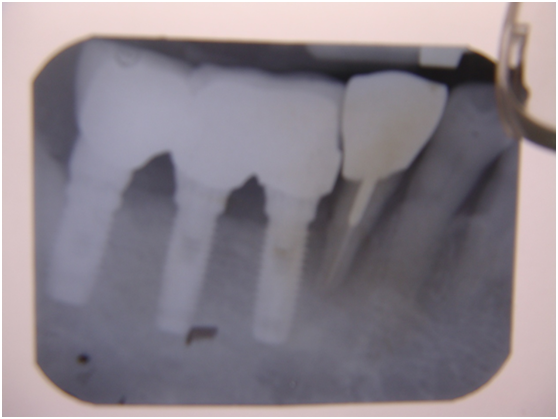

完成後大約半年至一年進行一次例行性追蹤檢查,並無特別問題。以下為96/08/13時的追蹤小片,可以見到當時三顆植體的骨高度並無顯著變化。但右下第一小臼齒此時發現有搖動度增加的情形,當時對該顆牙做了咬合調整,降低咬合功能負荷,希望能有所改善。

96/08/13